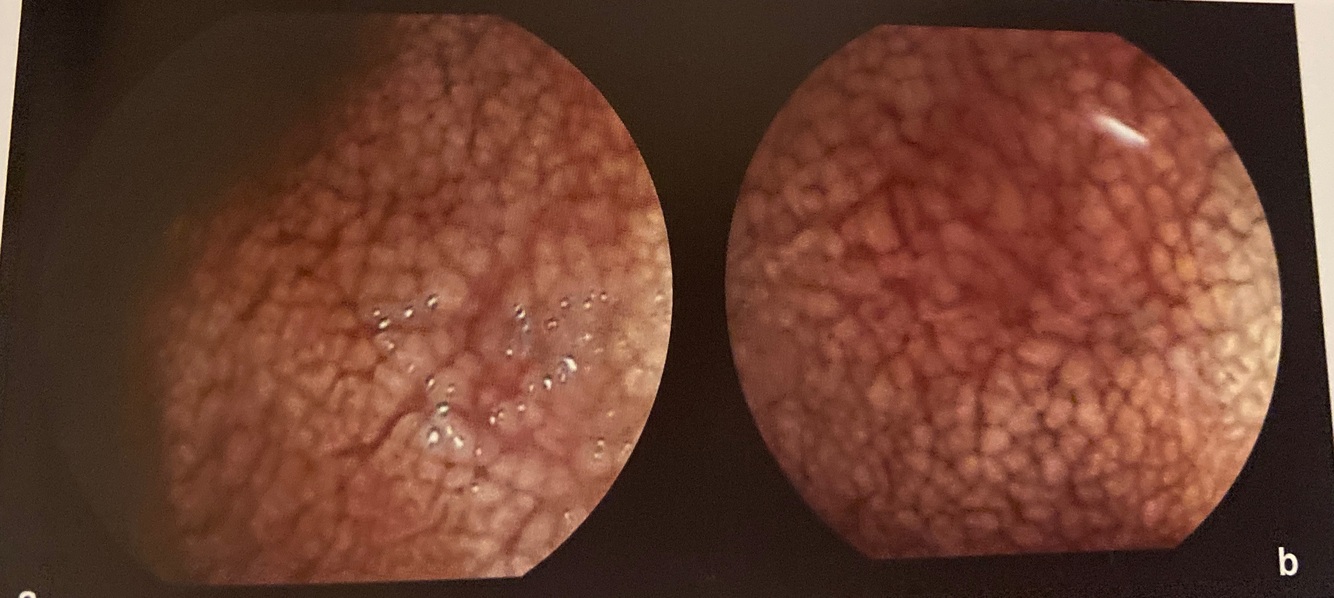

vilosidade mais globosa, com aparente achatamento e coloração brancacenta:

Doença de Wipple

Descrição duodenal

a e b segunda porção duodenal com recurso de magnificação de imagem, evidenciando vilosidades intestinais achatadas e alargadas e de coloração brancacenta.